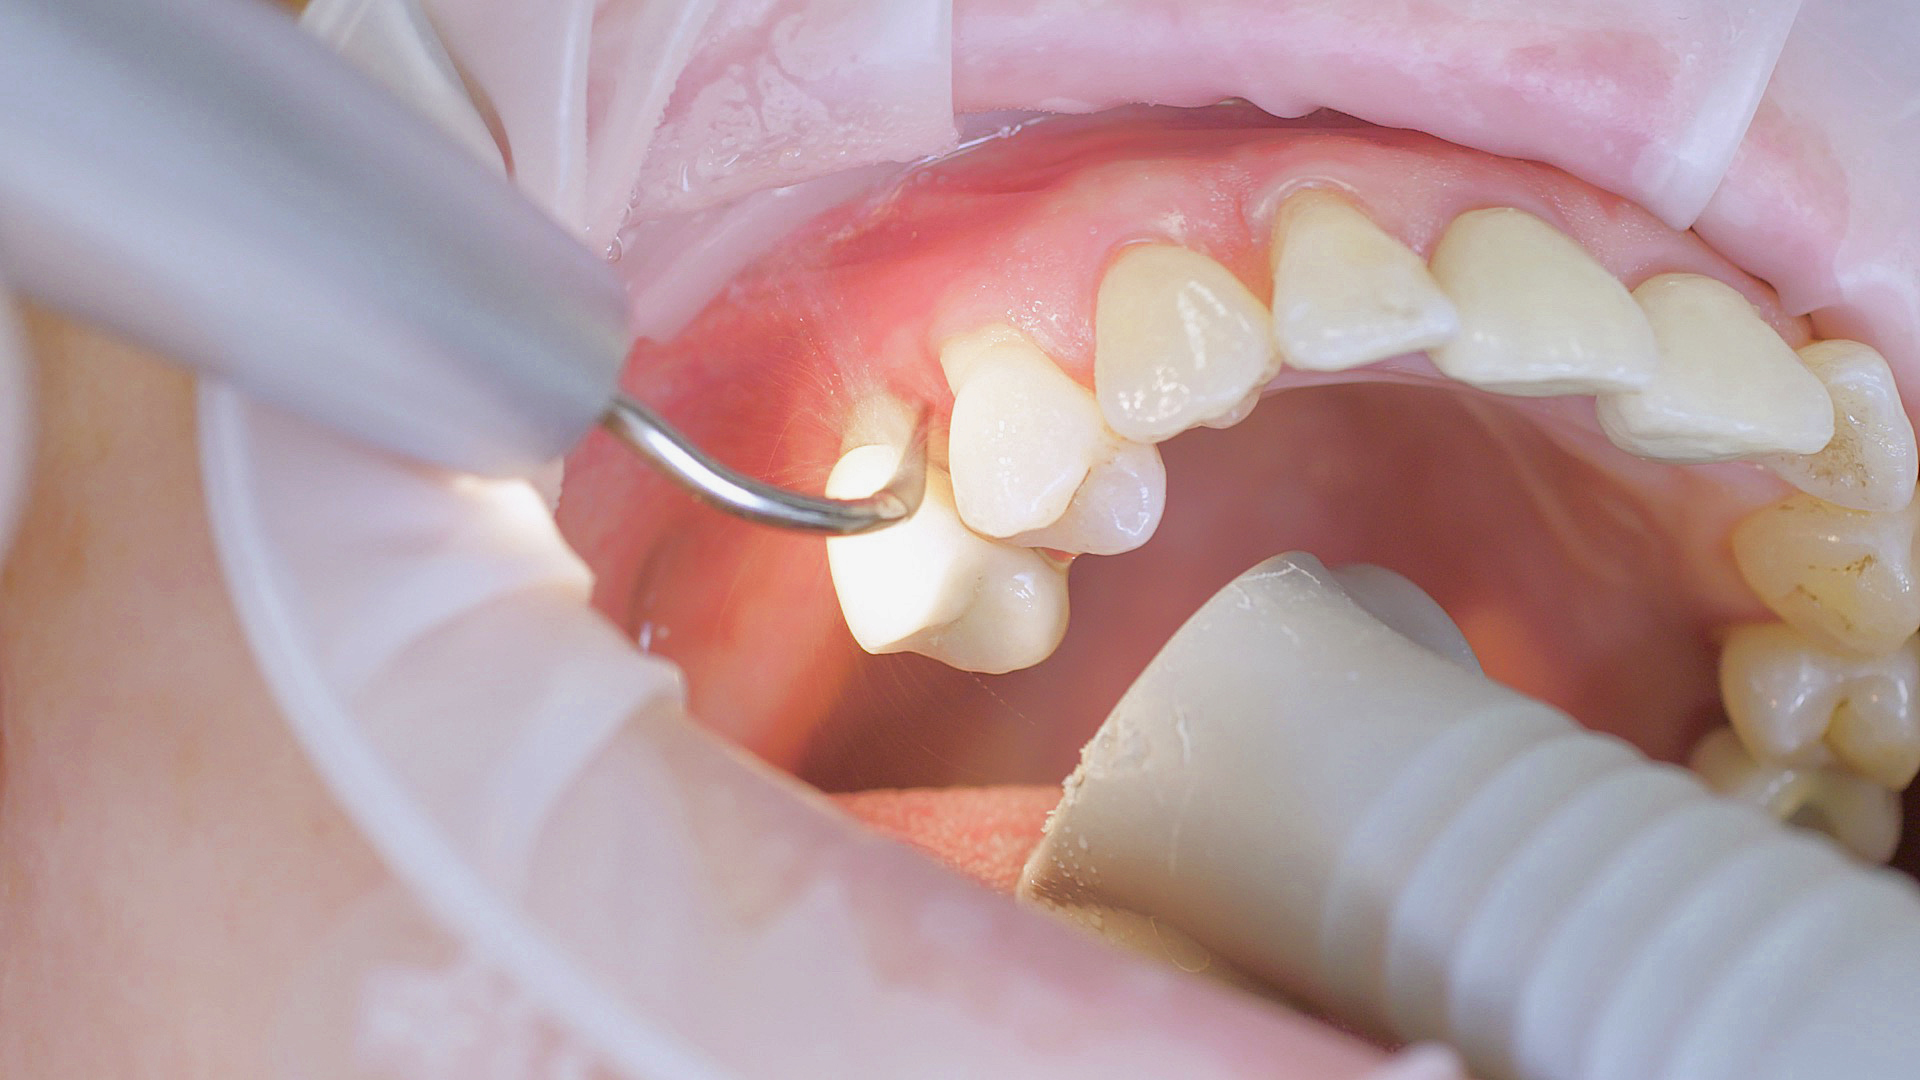

Healthy peri-implant tissue does not show any signs of redness, swelling or bleeding, neither does it secrete pus when probed.[5] Based on the consensus document, Prof. Giovanni Salvi explained the importance of regu- lar probing — preferably with a flexible probe, as implant components often tend to obstruct the procedure.[5] In the case of mucositis or initial peri-implantitis already being present, the non-surgical removal of hard deposits and biofilm should be attempted first. For this purpose, ultra- sonic power and special instruments designed to protect the implant should be employed (Fig. 3; piezo scaler Tigon+ with 1I, W&H). In case of no remission, the recall frequency needs to be increased. However, specific recommendations, applicable to individual cases, are not yet available in this context.[15]